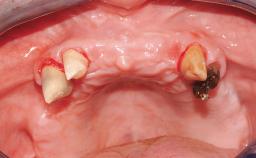

A 35-year-old Caucasian female presenting with advanced periodontal disease involving both the maxillary and the mandibular dentition was referred for evaluation. The patient, a non-smoker in good general health, requested treatment for recurrent periodontal abscesses, tooth mobility, and discomfort during chewing, as well as restoration of her missing teeth with a fixed prosthesis to improve mastication and esthetics. All residual maxillary teeth exhibited plaque deposits, deep pockets, bleeding on probing, and class III mobility and were evaluated as hopeless. All residual mandibular teeth except tooth 37 could be maintained after periodontal therapy.